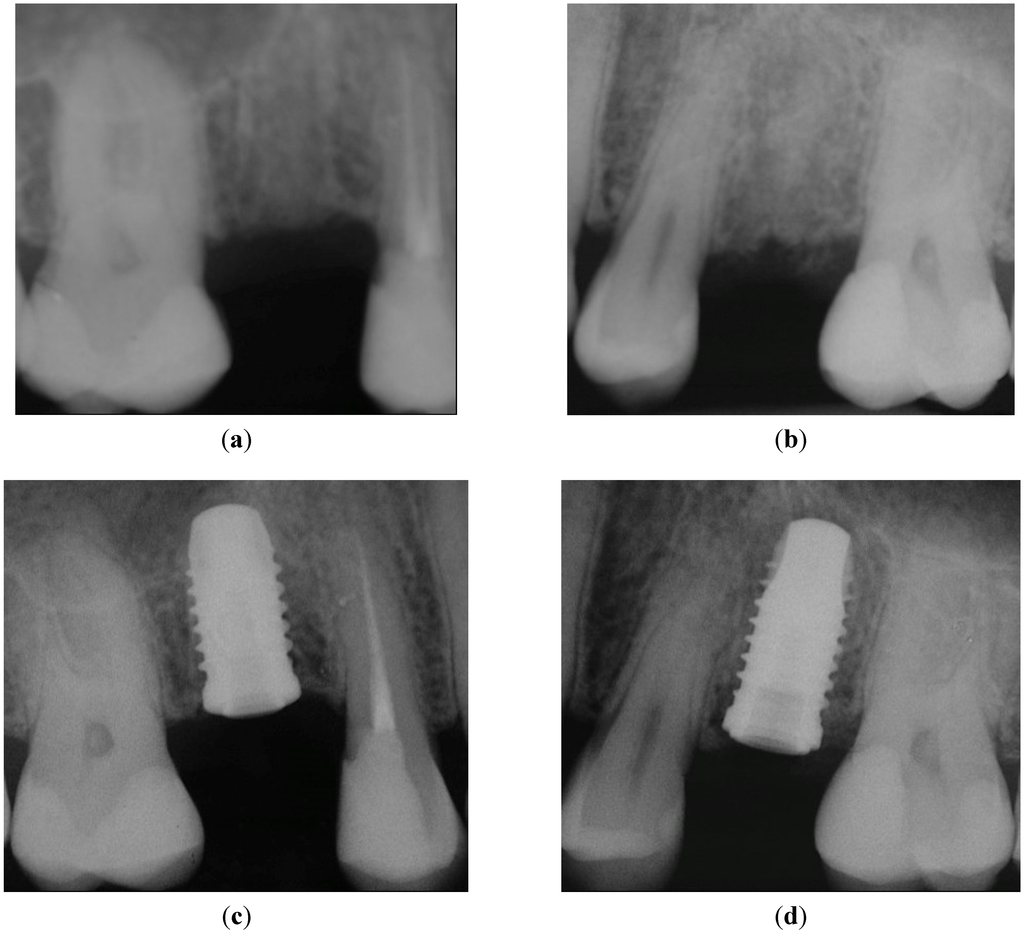

Figure 4.

X-rays taken before implant insertion and immediately after implant placement: (a) healed crestal bone in Position 15; (b) healed crestal bone in Position 25. No pathological signs were present after implant placement of both implants: (c) Position 15, implant with PFS; (d) Position 25, StE implant.

The same question applies to soft tissue changes. In the presented study, the implants have been placed by experienced surgeons that achieved a very favorable clinical outcome (PD < 4 mm, Figure 3a). It seems unlikely that such an optimal outcome can be further improved significantly by PFS. The documentation of a case from the presented collection is shown below to support this notion. A 35-year-old female patient required the replacement of the second premolar on both maxillary arches (Positions 15 and 25; FDI). Minimally traumatic tooth extraction was done eight months before implantation; consequently, the crestal bone immediately before implant placement was fully healed (Figure 4a and Figure 4b, Positions 15 and 25, respectively). Implants were placed with no complications. Following randomization, the PFS implant was inserted on the left (Figure 4c; Position 15), whereas StE was placed on the right side (Figure 4d; Position 25).